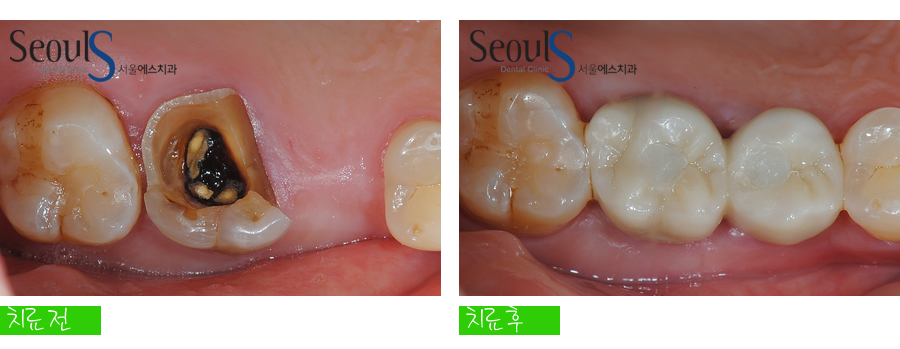

임시치아를 결합한 모습~~ 측면

임시치아 과정을 거쳐 최종 치아를 결합한 모습입니다

예쁘고 튼튼한 치아가 결합된 모습입니다

임시치아 과정을 거친 후 최종 치아를 제작 및 결합했기 때문에 불편함 없이 치아를 잘 사용하셨습니다..^^

치료 전후 치아 모습입니다

상실된 어금니, 임플란트를 식립해 치아를 복원했습니다

이쁘고 튼튼하게 치료가 마무리된 모습이죠^^